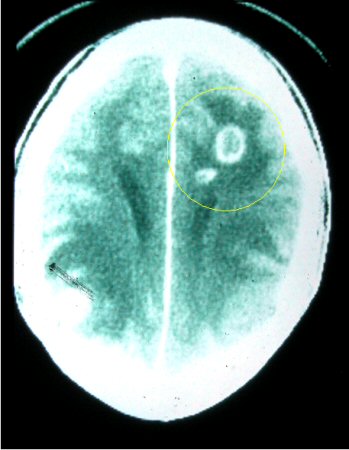

Toxoplasmose

Patologia cerebral: embora esta seja uma patologia do tecido de camundongo, ela é muito semelhante em aparência à do tecido humano

Do acervo de Louis M. Weiss, MD, MPH; uso autorizado